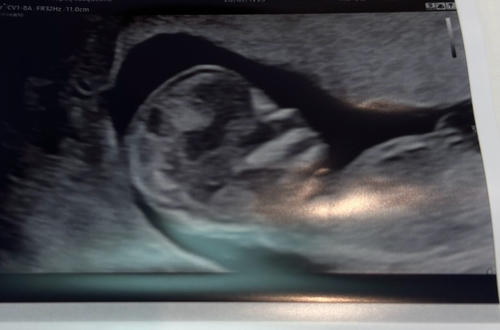

14+6 🥰 mit Elle, Speiche und Hand :)